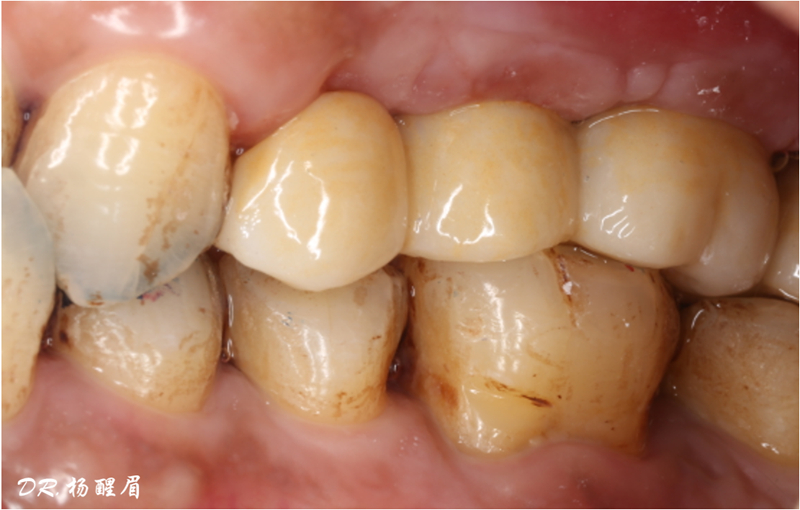

®袖口形態(tài)

®基樁形態(tài)

修復完成